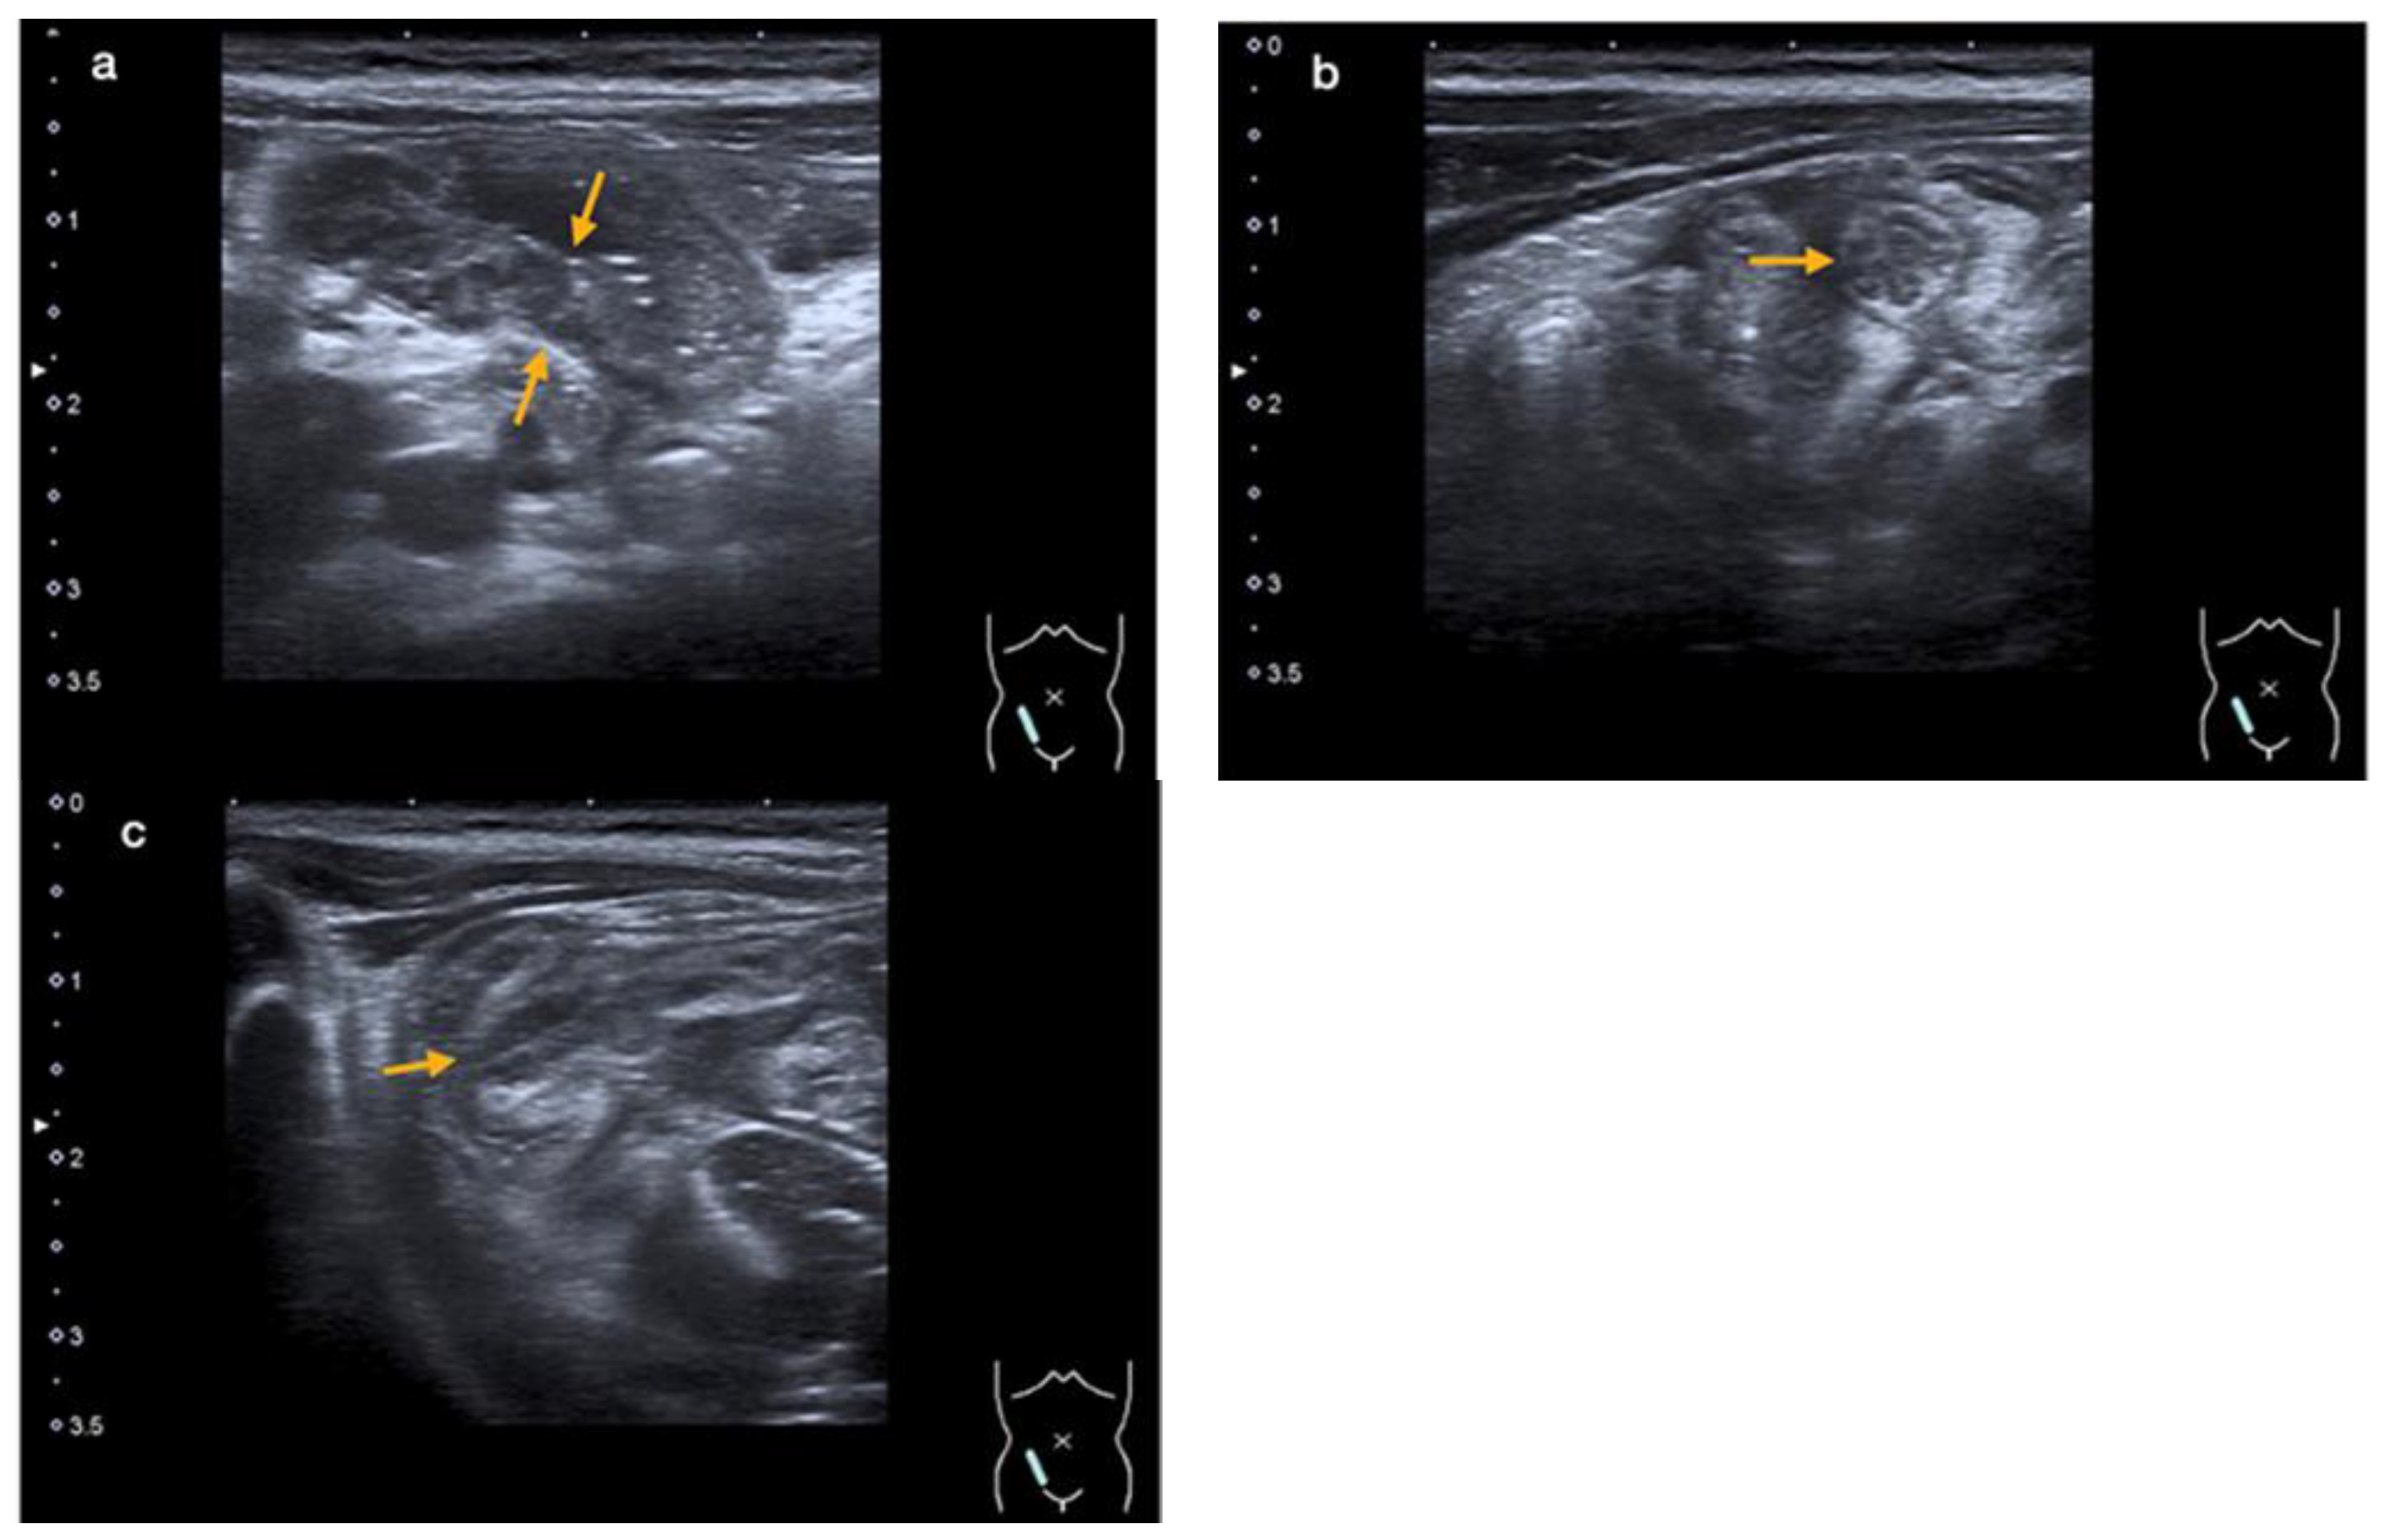

3. Case 2

3.3. Diagnostic Evaluation